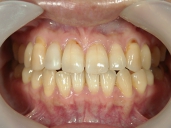

矯正歯科 治療前 正面

矯正歯科 治療後 正面